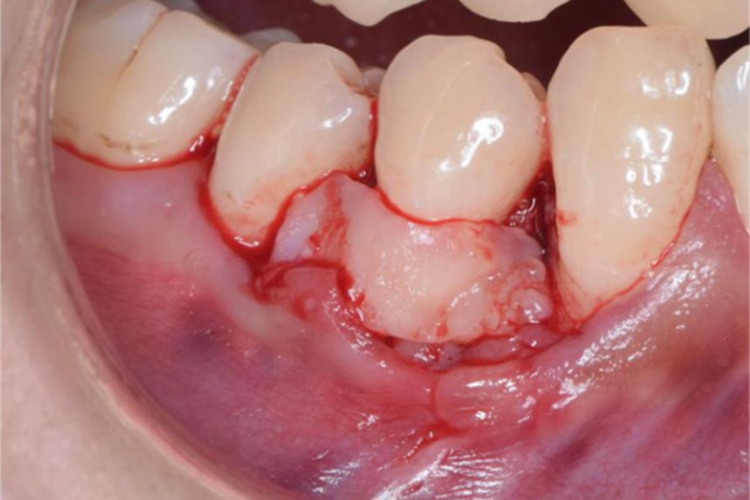

做切口:在肿瘤基底部蒂外0.2-0.3厘米的正常黏膜上做切口,切口深及骨面。

剥离肿瘤:自骨面剥离肿瘤,完整切除。常规需拔出受累牙齿,用刮匙及咬骨钳除去被波及的牙周膜、骨膜及牙槽骨,以防复发。需注意妊娠期牙龈瘤切除可不拔牙及去除牙槽骨。